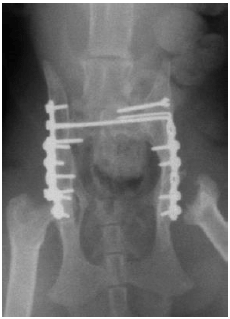

4. 交通事故にあった子猫の骨折

![]() |

交通事故後のレントゲン写真で、子猫の骨盤が正面から映っています。 本来くっついているはずの骨盤と腰骨がずれて脱臼しています。(赤矢印) 骨盤そのものも折れています。(黄矢印) |

手術後のレントゲン写真です。 骨盤と腰骨の脱臼を直し、骨盤の骨折も元に戻して固定しました。 太ももの骨の付け根は、一つ前の写真の赤線のラインで切り落としてあります。 「骨を切り落とす」というと痛くて残酷そうにも思えますが、実際にはこの逆で、この処置を行わないと痛みが取れず、子猫が辛い思いをすることになります。 この子は無事に成長し、現在は元気に走り回っています! |